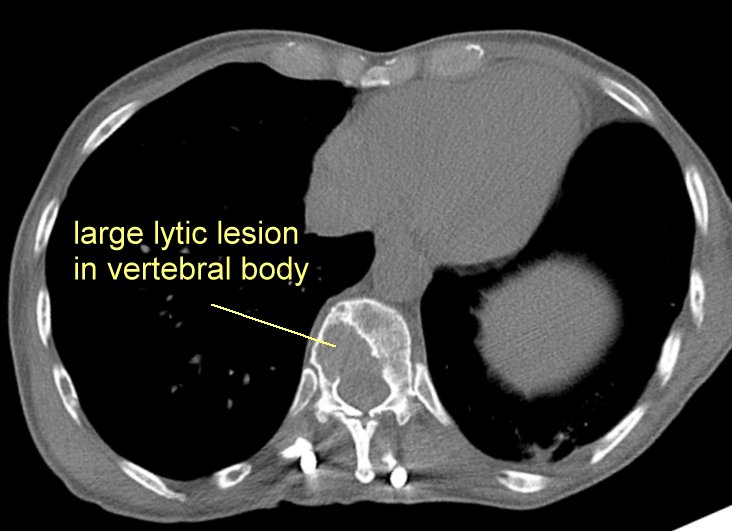

Multiple Myeloma / Plasmacytoma

Images of myeloma in the bone: (note that the goal is to vigorously treat the myeloma so

that the bones do not become this brittle.)

#8 Advanced disease in the thoracic spine

here and

here